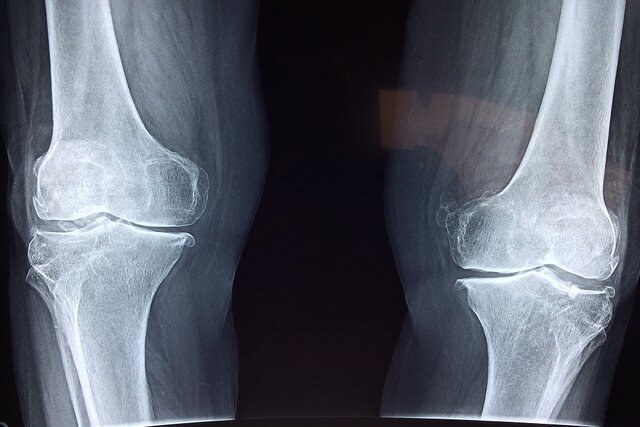

آسیب به استخوان‌ها

نخستین نگرانی، تاثیر منفی بر سلامت استخوان‌هاست. مصرف نوشابه و الکل هر دو با کاهش تراکم مواد معدنی استخوان و افزایش خطر شکستگی مرتبط است. مصرف نوشابه به‌دلیل وجود اسید فسفریک می‌تواند تعادل کلسیم و فسفر را بر هم بزند و خطر شکستگی لگن را افزایش دهد. مصرف الکل نیز با کمبود کلسیم، اختلال‌های کبدی و کاهش ویتامین دی همراه است که همگی به تضعیف استخوان‌ها منجر می‌شوند.

دومین تهدید، افزایش خطر زمین‌خوردگی است. با افزایش سن، تعادل بدن به‌طور طبیعی کاهش پیدا می‌کند و مصرف الکل این مشکل را تشدید می‌کند. تضعیف تعادل توام با ضعیف شدن استخوان‌ها، احتمال آسیب‌های جدی ناشی از زمین‌خوردگی را بالا می‌برد. الکل همچنین می‌تواند با برخی داروها تداخل‌های خطرناک داشته باشد.